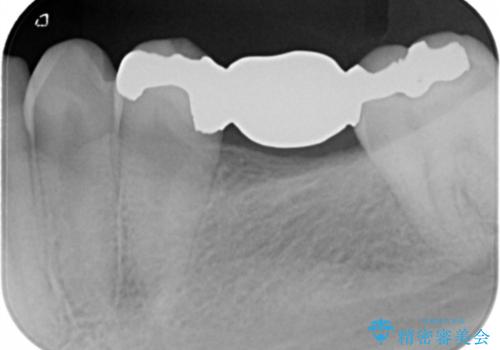

支台歯部分はインレー形態でしたが強度や維持性を考慮しクラウン形態への変更を計画しました。

後ろの歯が前に倒れ込んでいましたが問題なく治療を終えることが出来ました。